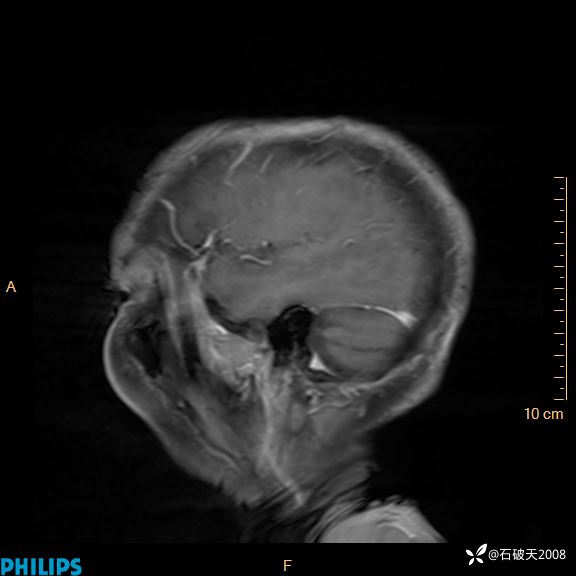

2020.11.14MR

增强矢状位